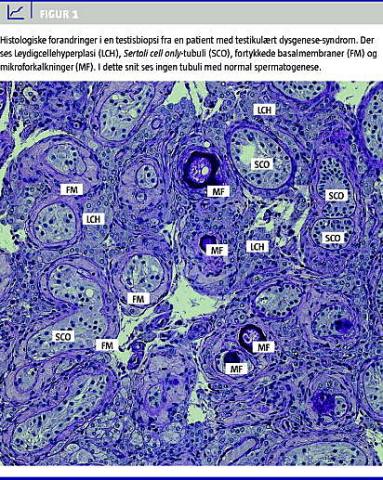

Ændringerne i sædkvaliteten samt forekomsten af testikelkræft, kryptorkisme og hypospadi har ledt til hypotesen om en mulig sammenhæng, kaldet testikulært dysgenese-syndromet (TDS) [10]. Ifølge hypotesen resulterer en dysgenese af testiklerne tidligt i fostertilværelsen i en risiko for medfødt kryptorkisme og hypospadi samt nedsat sædkvalitet og testikelkræft senere i livet [10]. I testisvæv fra patienter med oplagt klinisk TDS kan der påvises karakteristiske »dysgenetiske" histologiske forandringer, f.eks. mikroforkalkninger i vævet (Figur 1 ) [11].